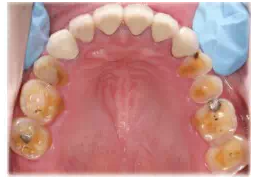

圖8患者J初診時(shí)的上頜咬合面可見舌尖明顯磨耗,橫牙合曲線呈上凸的倒曲線